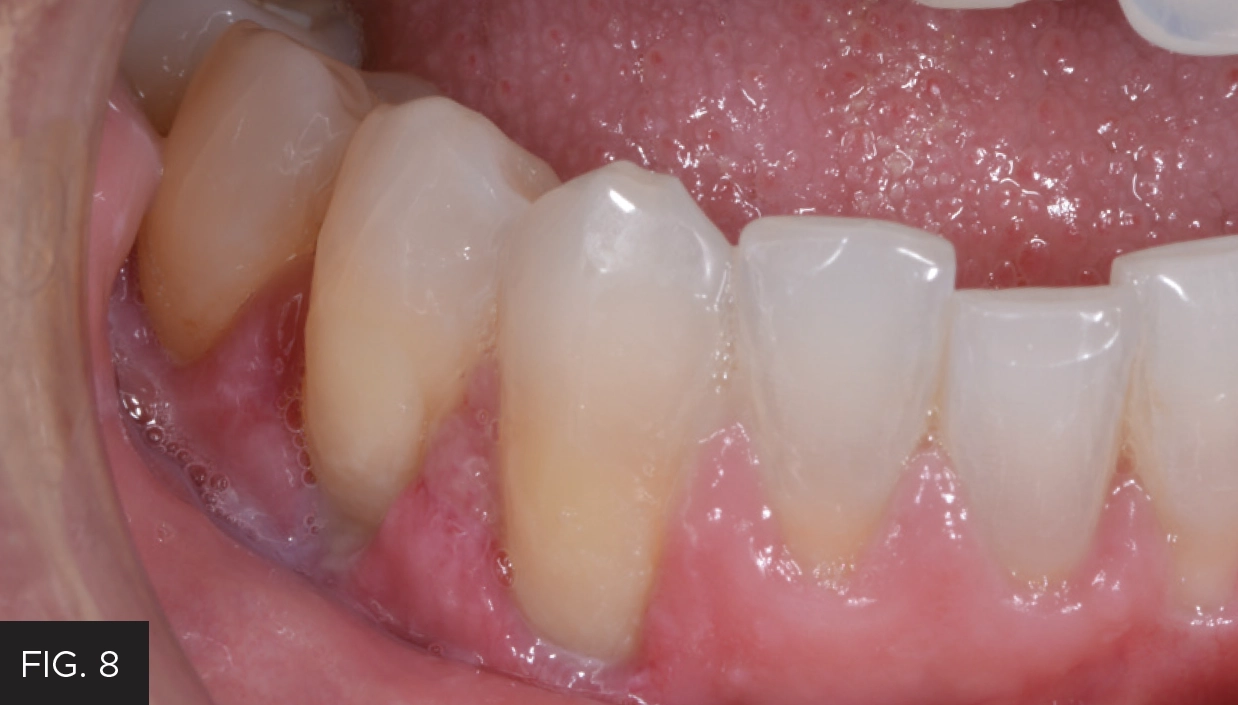

The one-week follow up photo shows how well the tissue healed after utilizing the Bluewave laser. (FIG. 8)